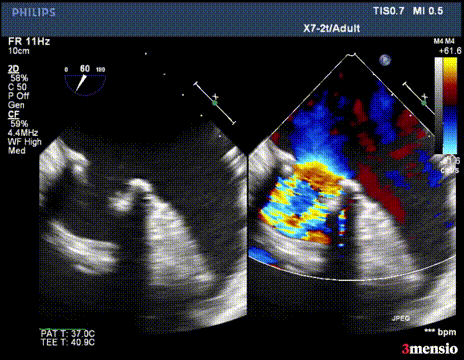

第一次切割后,导丝紧,血流分为两束

第一次切割后,导丝松,血流又合为一束,但方向改变

切割时拉紧导丝两端,不切割时,放松导丝,解除对瓣叶的压力后,用彩超观察血流方向,切割成功后,可以观察到彩超血流的改变。